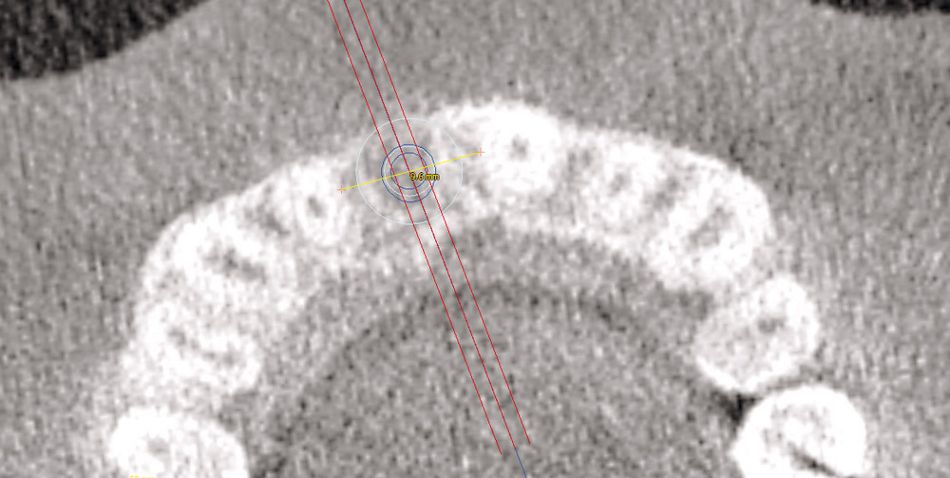

As the case was esthetically challenging, a surgical template was used to ensure correct implant position and angulation. Firstly, a virtual model of the botiss maxgraft® bonering was preoperatively designed using implant planning software and placed in the desired position in order to simulate the postoperative position of the implant (Figs. 3-4). Yet the preoperatively planned position of the bone ring still has to be accurately transferred into the clinical situation, so a template was manufactured to enable guided trephine drilling. Just as the implant can be positioned preoperatively, so it can be placed in a predictable fashion during surgery through the bone ring into the alveolar bone using the template.

As part of the planning process, the specific size of the bone ring had to be decided on. The maxgraft® bonering 4.1 (botiss biomaterials GmbH) was chosen, because an implant with a diameter of 4.1 mm (Straumann® Bone Level Implant Roxolid® SLActive®) had been selected to esthetically restore the missing tooth. Accordingly, the implant template was then designed and manufactured for accurate surgery (Figs. 3-4, 10).